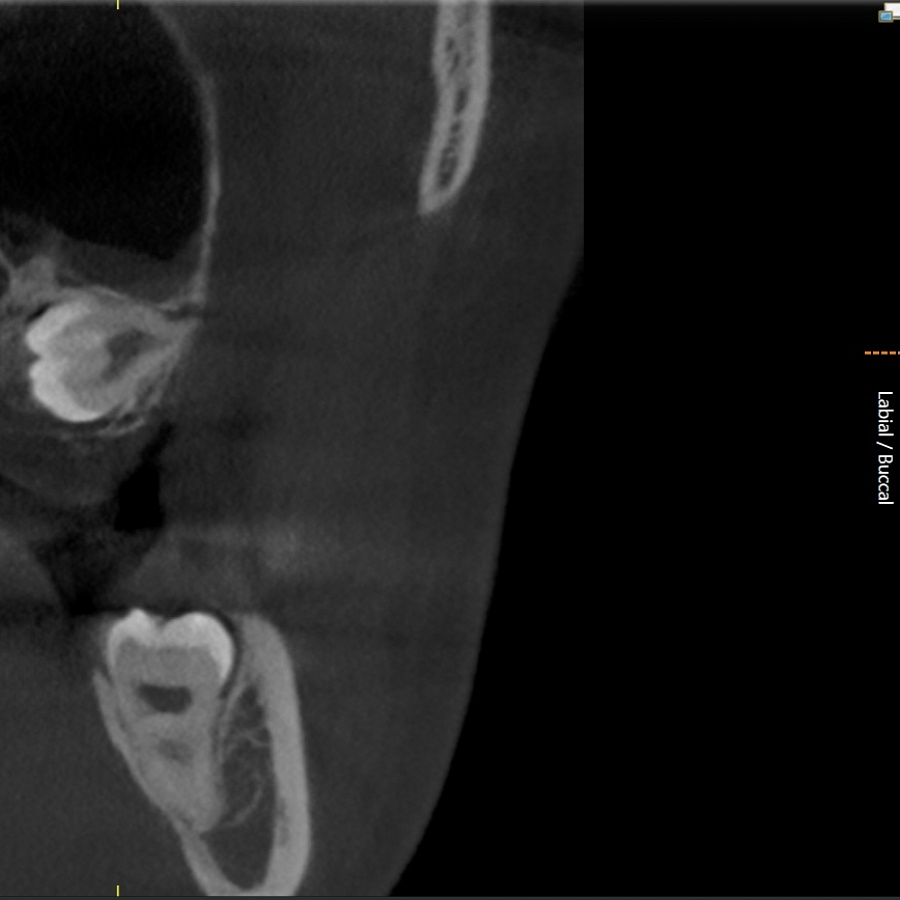

Зуб не прорезался, лежит горизонтально и направлен в сторону твёрдого нёба, мешает проведению ортодонтического лечения, выпрямлению зубных рядов. Около зуба проходит несколько важных анатомических структур, которые нельзя задеть, плюс зуб полностью погружён в костную ткань.